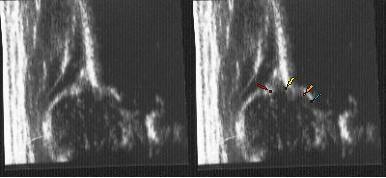

Typ D(kąt jak Typ IIa) typ IIA (kąt I) dziecko 3 tygodniowe pomiar katów @ i B przez program w aparacie usg

po następnej wyznaczonej kontroli za 2miesiące w 3m.ż typ IV i I